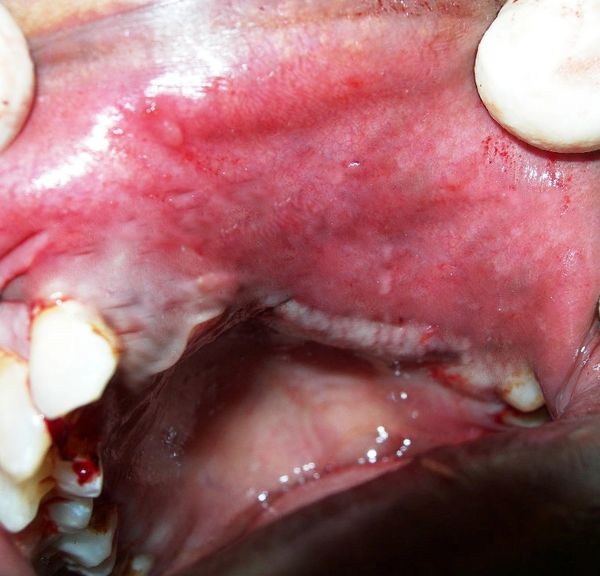

- Cyst and Tumour of Jaw

- Cyst & Tumour of Jaw/Face